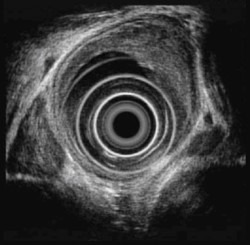

식도암에서 식도초음파 내시경

위에서 말한 일반적인 식도내시경의 경우에는 식도내강의 표면만을 관찰하도록 되어있어 암이 얼마나 깊이 파고 들어 갔는지는 알기 어려운 단점이 있습니다. 흉부 전산화단층촬영 등의 방법도 있지만 정확한 깊이는 알기 어렵습니다. 초음파 내시경검사는 식도내에 초음파기기를 삽입하여 식도벽을 통해 검사를 시행하므로 식도암의 침범 정도에 대해 세밀하게 알 수 있습니다. 뿐만 아니라 식도암이 대동맥이나 척추, 기관 같은 식도 주변의 기관으로의 침범여부도 정확히 알 수 있으며, 암의 식도 주변의 림프절 침범여부도 비교적 정확히 알 수 있으며, 식도를 통하여 조직검사를 할 수 도 있습니다.